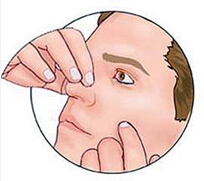

带状疱疹病毒性睑皮炎

疾病介绍:本病是由带状疱疹病毒感染三叉神经半月神经节或三叉神经第一支所致,多见于老年人或体弱者。多有发热、乏力、全身不适的前驱症状。随后病变区出现剧烈…【详细】

睑板腺梗塞(结膜结石)

疾病介绍:睑板腺梗塞是睑板腺排泄管闭塞,分泌物积存日久钙化形成小结石。睑结膜下可透地黄色沉着物。一般尤不适。当小结石的尖锐棱角突出于结膜面时,则引起异…【详细】

睑板腺囊肿(霰粒肿)

疾病介绍:睑板腺囊肿足睑板腺排出口阻塞,腺体分泌物潴留在睑板内,对周围组织产生慢性刺激而引起的特发性无菌性慢性肉芽肿性炎症。多见于青少年或中年人。一般…【详细】